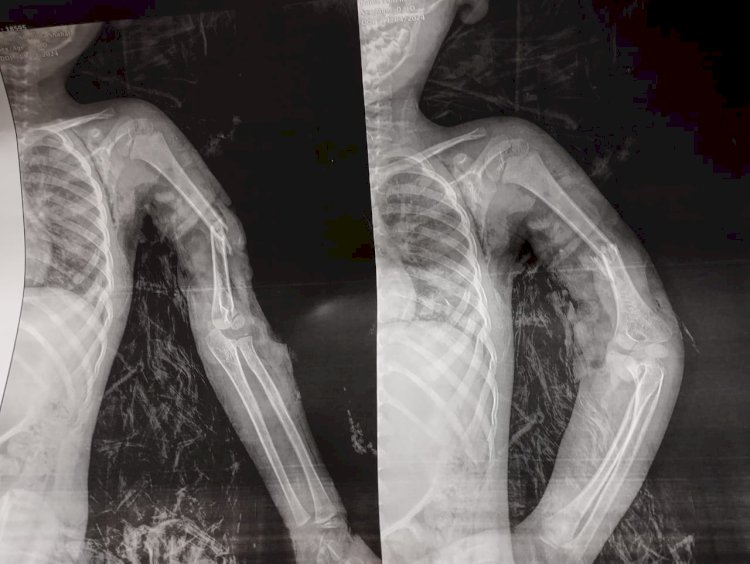

وقال الدكتور مجدي القاضي عميد كلية الطب البشري، أن الطفل المصاب وصل إلى المستشفي في حالة حرجة جداً بعد تعرضه لإصابة مباشرة من ماتور ري زراعي، وبتوقيع الكشف الطبي عليه من قبل أطباء الاستقبال والطوارئ بمستشفي سوهاج الجامعي، فقد تبين وجود قطع في الأعصاب والشرايين المغذية للطرف العلوي الأيسر مع تهتك بالانسجة وكسر بعظمة العضد اليسري.

ومن جانبه أكد الدكتور عبدالرحمن الشيخ رئيس قسم العظام، أنه علي الفور تم التعامل مع الحالة وتم تثبيت الكسر بواسطه مسمار نخاعي مرن وتم توصيل الشرايين المغذية للطرف العلوي مع أخد رقعة وريدية من الطرف السفلي، مبيناً أن الحالة الان بصحة جيدة وفي طور التحسن مع رجوع الدورة الدموية للطرف العلوي.